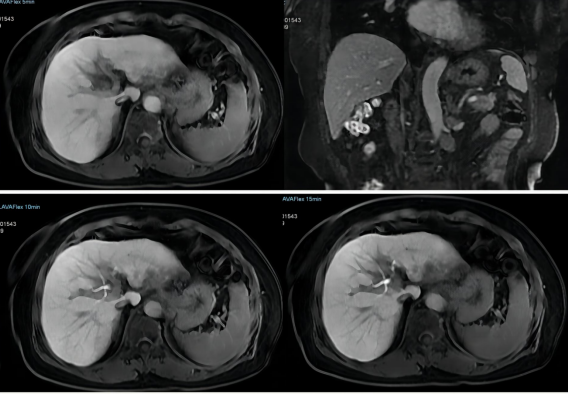

(四)肝臟定量磁共振成像及肝膽特異性對比劑成像普美顯(釓塞酸二鈉)注射液是一種肝細胞特異性對比劑,可以提供普通磁共振增強的圖像,還可以獲得清晰的肝細胞特異性圖像,肝特異性對比劑磁共振增強的優(yōu)勢在于能發(fā)現(xiàn)小于1cm的肝內(nèi)病灶,為肝癌提供特異性的診斷和鑒別診斷信息,提高肝內(nèi)病灶的檢出率,有助于肝內(nèi)病變的準確診斷。

圖片

肝臟定量磁共振成像

肝特異性對比劑MRI增強檢查